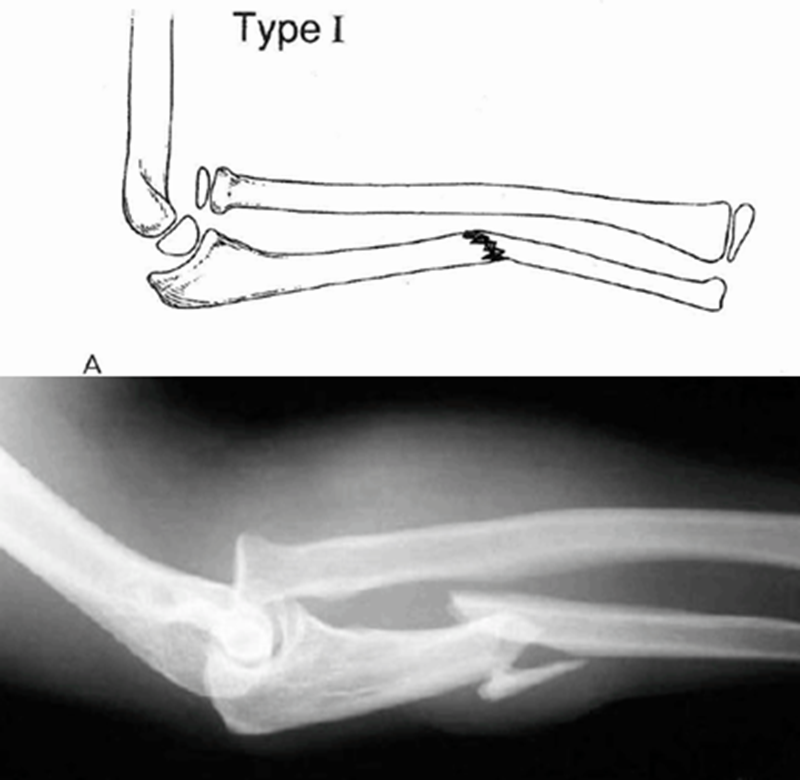

目前临床上主要采用Bado分型方法,即根据尺骨骨折和桡骨小头脱位的方向,分为Ⅰ、Ⅱ、Ⅲ、Ⅳ四型。

Ⅰ型(伸直型):桡骨头向前脱位(前脱位),尺骨骨折断端向前方成角,为儿童常见的骨折类型,约占 55%~75%。1985年LETTS等根据尺骨骨折的特征将Ⅰ型孟氏骨折进一步分为3型:A型为尺骨弓形变,B型为尺骨青枝骨折,C型为尺骨完全骨折。

受伤机制:肘关节于过伸位损伤,桡骨小头因肱二头肌强力收缩而发生前脱位,身体重量移于尺骨造成骨折。